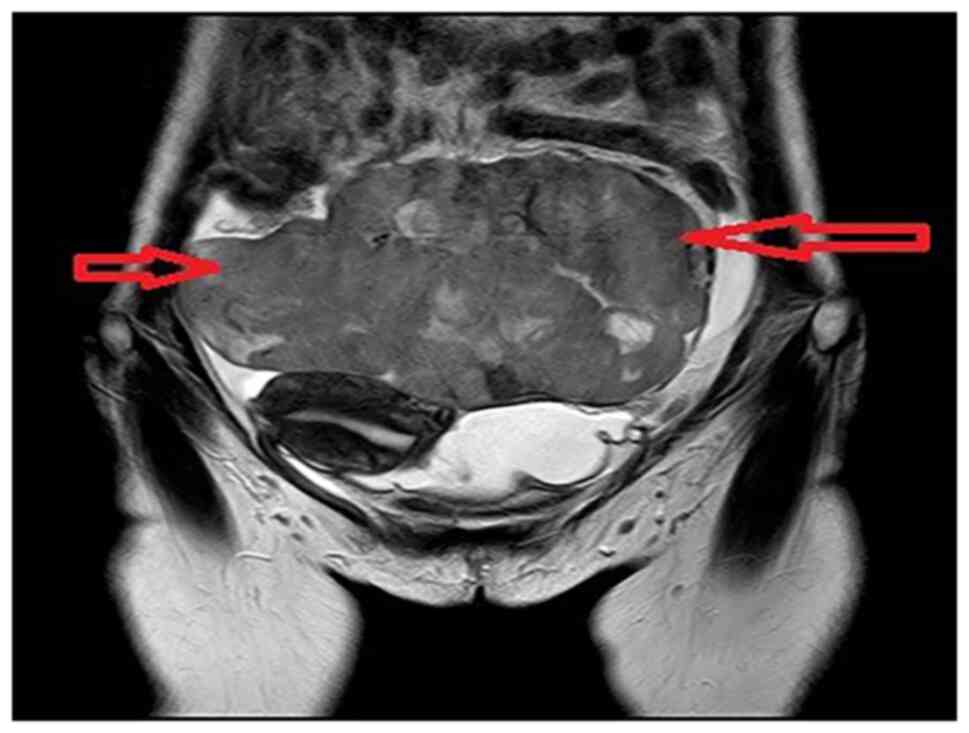

Double‑hit primary lymphoma (MYC and BCL2) in the bilateral ovary: A case report

Lymphoid neoplasm with 18q21.3/BCL2 and 8q24/MYC translocation to immunoglobulin genes as dual‑hit lymphoma in female bilateral ovaries is rare and has a poor clinical outcome. The present study reported on the case of a 33‑year‑old female, who was admitted to the hospital due to lower abdominal distension aggravated during defecation but with no obvious inducement. The B‑ultrasound revealed bilateral adnexal solid masses and the pathological examination indicated advanced B‑cell lymphoma (HGBL) with MYC and BCL2 gene rearrangement. The patient then received R‑CHOP treatment, but the effects were poor. Rare extranodal HGBL presentations with MYC and BCL2 rearrangement should be considered in the differential diagnosis of masses at unusual sites, such as the adnexa. Due to their aggressive nature, early and prompt recognition of these lymphomas is essential for appropriately administering therapies.